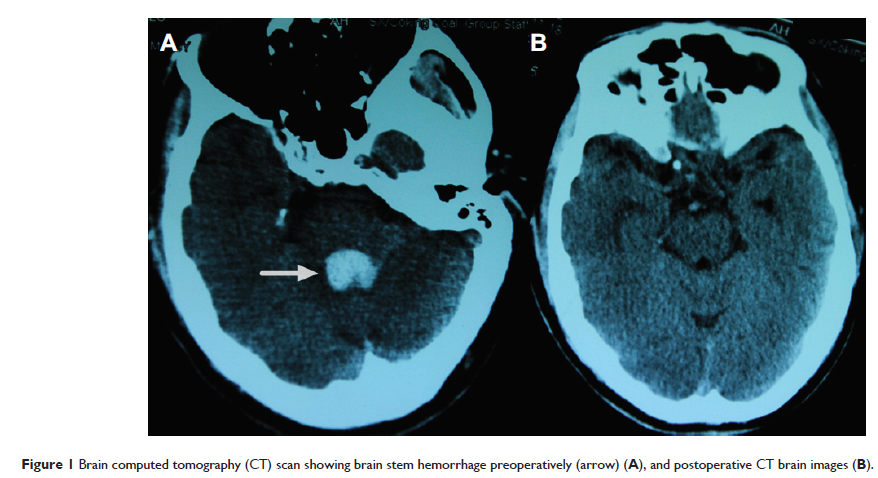

Case Report

- 作者:Qing-ya Cui, Hong-shi Shen, Tian-qin Wu, Hai-fei Chen, Zi-qiang Yu, Zhao-yue Wang

- 期刊:Drug Design, Development and Therapy